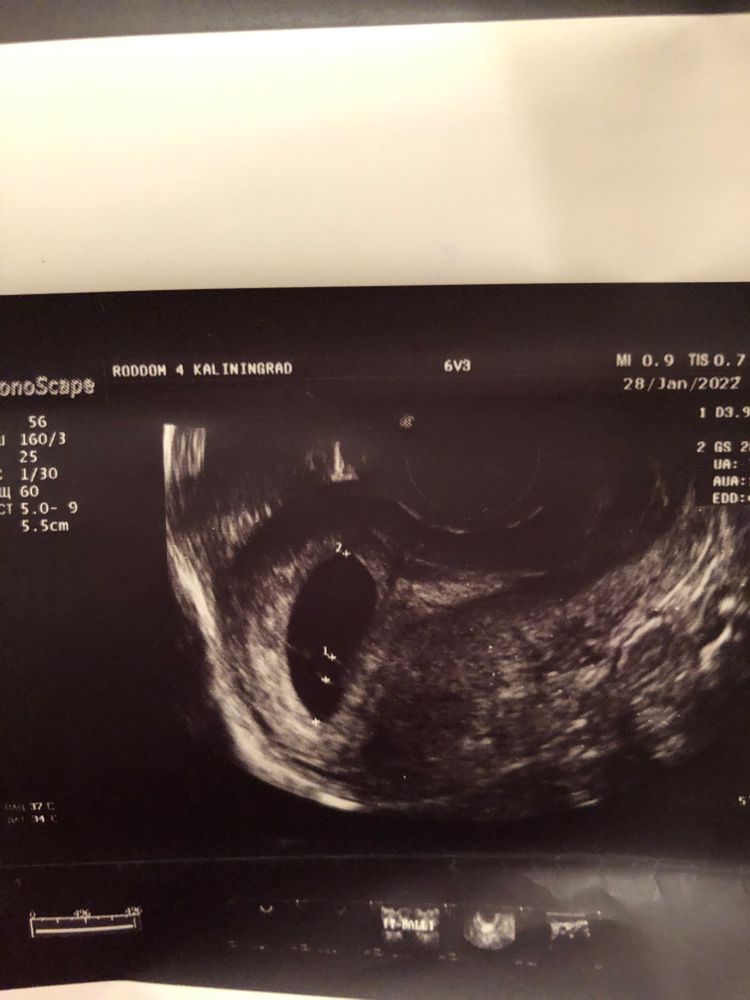

Последние месячные были 1.12, срок должен был быть 8 недель 6дн. На 7-й недели сильно болел живот, обратилась к дежурному геникологу в жк, т.к на учёт у нас ставят только с 8-у недели. Меня осмотрели, сказали все в порядке, назначали через неделю узи. Поставили на учёт, через пару дней пошла на узи, где мне говорят что не слышно сердцебиения. Спрашивают про симптомы тошнит, не тошнит и т.д, нет ли выделений(выделений нет, тошнить продолжает, сплю постоянно, живот не тянет, температуры нет, да и в целом ни единого признака замершей нету). Меня начали успокаивать и отправили к доктору, сказали есть вероятность что срок маленький, и ставят мне срок 5 недель 6 дней. Пошла к доктору, доктор сказала делать ХГЧ в динамике, и через неделю на повторное узи. Сделала на след день ХГЧ, не выдержала и через три дня(сегодня) я пошла на узи в другую клинику. Там мне сразу же сказали, что плод не развивается, и ставят срок 6-7 недель, так же размер эмбриона(ктр) при этом 3,9, а три дня назад был 3,22. Получается по размеру это и есть 6-7 недель, но плод увеличился же ведь… Меня и слушать сегодня не хотели, повели сразу к доктору, тот говорит надо делать срочно медикаментозный аборт. Я говорила про то, что второе ХГЧ ещё не делала, на это мне говорят, что уже бессмысленно его ждать все понятно, на данном сроке сердцебиение должно быть ясным. Записали на завтра на аборт. Я вся как в тумане, решила поехать и сделать ещё одно узи в другой клинике. Прихожу, начинаю объяснять, мол почему ставят разные сроки и размеры, спрашивать почему симптомы беременной у меня не пропали, а симптом замершей нет никаких. Говорят на это, что это аргумент. Пошли на само узи, тут же мне показывают что у меня два пя, и что у меня однозначно неразвитая беременность, ставят диагноз что у меня двойня и замершая. Я снова, как в тумане потерялась, забыла про все вопросы, в расстройстве, ушла. И только потом до меня дошло, что вероятно с меня хотели содрать деньги(за аборт и восстановление). Завтра на аборт не пойду, сделаю второе ХГЧ, и после на ещё одно узи. Надеюсь на чудо.

Прикреплю фото всех узи. И да, ХГЧ первое пришло там результат на 76037, результат в пределах нормы 7-9 недели.